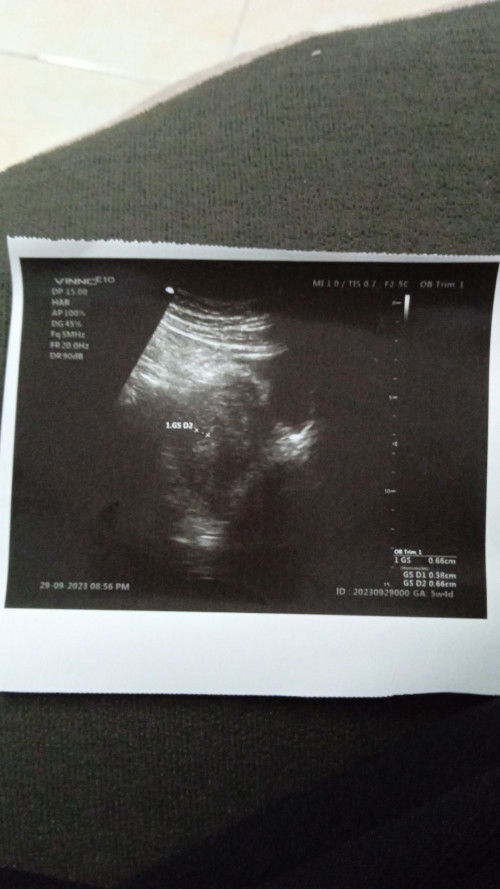

salam,,takdi sya prgi scan 5w4d ad nmpk bulat tapi kecil tak boleh nk ukur,tpi dktr ad ckap sesuai ng 5w rahim pun nmpk kembang mcm pregnant lpstu klau xpreg akan nmpk darah period akn period tpi xde pun darah akan period,prgi scan sbb nk sdpkan hati sllu je fkir ada bby tak dlm prut ni terasa alahan smkin kurang baru ni ad je pergi kk sbb swab keptihan sebelum preg ad +ve gbs,test air kencing +ve dkat kk p dktr xscan sbb msih awal katanya,tpi terfikir tulah.tpi kecil buat sya terasa sedih bimbang. Ada ke macam saya tapi kandungan lpastu membesar dgn baik,bleh share bg kata semangat kat sya,pdhal masa ank first sya cnfirm preg 4w xnmpk apa2 pun repeat baru nmpk bby,,tpi ntahlah yg ke2 ni sya takut sgt xjdi buat sya sedih fkir mcm2.smge kandungan sya membesar dgn baik,aamiin